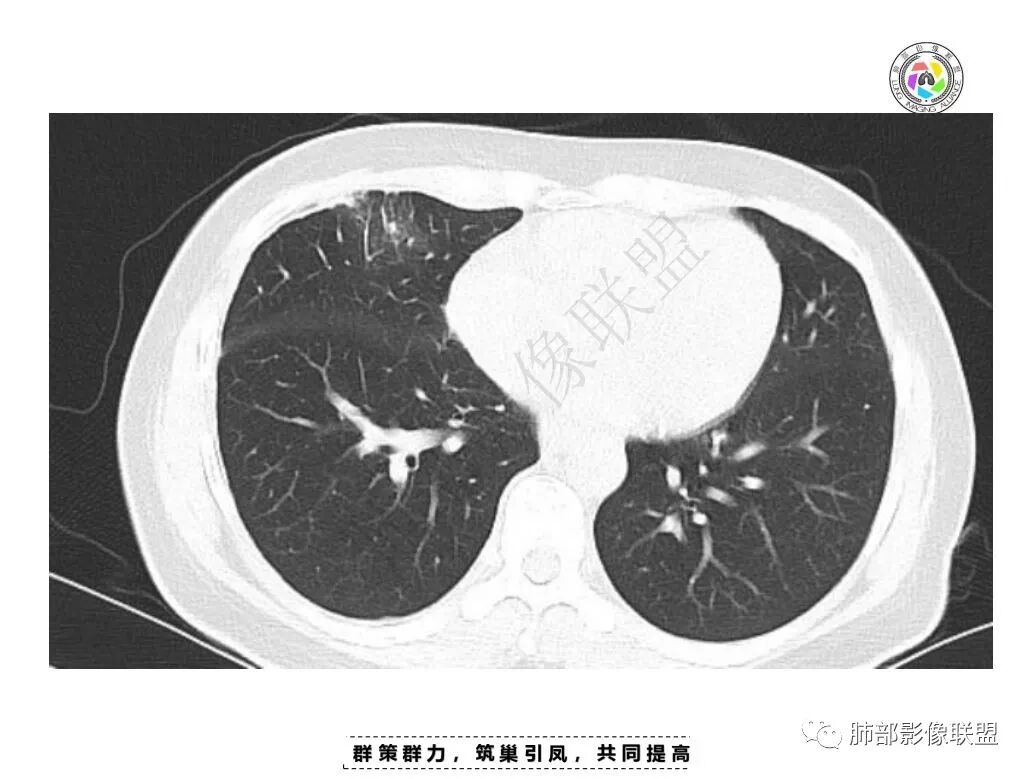

两肺可见数枚实性小结节;右肺胸膜下见丘状凸起,较大者周围可见支气管血管束,增强边缘强化,首先考虑慢性炎性肉芽肿,鉴别球形肺不张。

女,34,胸痛1年余。胸部CT:两肺上叶小结节。右肺胸膜下两个结节,宽基底与胸膜相贴,胸膜尾;右前胸膜下结节影,胸膜局部增厚、糊墙,胸膜下脂肪间隙模糊,部分层面结节灶边缘毛糙、支气管血管进入,结节增强后内有片状坏死区,一月后复查有增大。慢性病史,多部位,多灶,多形性病变,肺内、胸膜都有病变,常规考虑结核等慢性特殊感染,鉴别淋巴瘤。

肺内多发小斑片状高密度影,密度不均匀,边缘稍平直

2.肺内多发斑片影,边缘光滑,支持炎性特点,不符合恶性侵犯的特点,一般恶性肿瘤侵犯肺内往往边界不清,复查附近病灶有收缩,更加支持炎性病变;